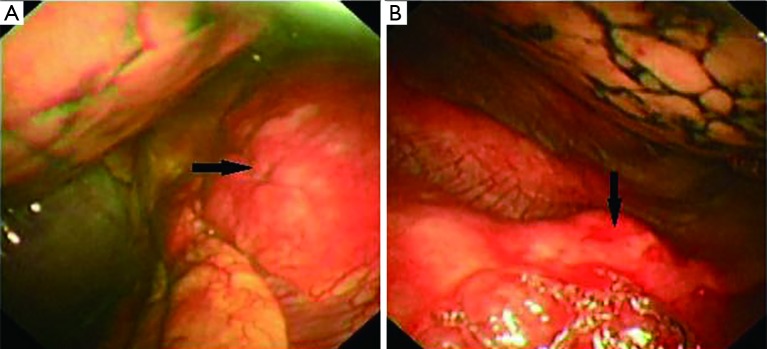

The bone marrow aspiration biopsy showed that hyperplasia of original plasma cells (1.5%) and active hyperplasia of naïve plasma cells (15.5%) (Figure 2). A thoracoscopic pleural biopsy of right side through video-assisted thoracic surgery was performed. Multiple nodules of pleural surface and partial lung collapse could be seen (Figure 3). The pathology of the specimen revealed abnormal proliferation of plasmocytes on hematoxylin and eosin (HE) stains. The immunohistochemistry test of the specimen showed: CD31 (+), CD34 (+), Ki67 (50%+), CD138 (+), CD38 (+), Kappa (+), Lambda (–), MUM1 (+) (Figure 4).

Figure 4.

Pathology and immunohistochemistry of the pleural biopsy: (A) hematoxylin and eosin (HE) staining shows abnormal proliferation of plasmocytes. (B-I) are immunohistochemical staining including (B) CD138 (+), (C) Kappa (+), (D) Ki67 (50%+), (E) CD34 (+), (F) MUMI (+), (G) Lambda (–), (H) CD31(+), (I) CD38(+). CD138 and CD38 positive usually represent malignant plasmacyte disease; Kappa (+) and Lambda (–) means kappa light chain multiple myeloma. Ki-67 (50%+) represents the growth fraction of the cell population is over 50%. CD34 (+) here represents hematopoietic disorder. MUM1 is a key regulator of several steps in lymphoid, myeloid, and dendritic cell differentiation and maturation. CD31 (+) here represents malignant plasmacyte diseases. The magnifications are all of 400.